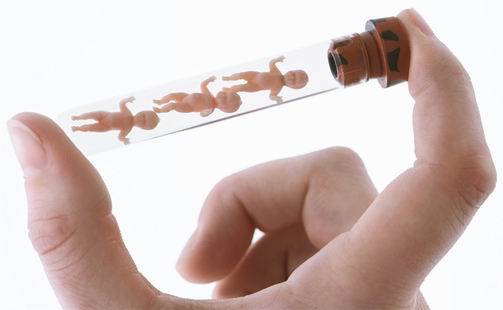

中马吉孕:准备做试管婴儿时,需要注意什么?

准备做试管婴儿时,需要注意以下几个方面的问题:健康状况评估:在开始试管婴儿前,夫妻双方需要进行全面的身体健康检查,包括遗传疾病筛...

准备做试管婴儿时,需要注意以下几个方面的问题:健康状况评估:在开始试管婴儿前,夫妻双方需要进行全面的身体健康检查,包括遗传疾病筛...

能够自然受孕成功是备孕夫妻的首选,但是如果备孕夫妻无法完成自然受孕成功的时候,做试管婴儿成为了备孕夫妻的希望。通过试管婴儿技术而...

试管婴儿有哪些过程步骤?1、促排卵治疗在做试管婴儿的过程中,需要获取多个的卵子以此确保有能够进行移植的胚胎,毕竟不是获取到的每一...

武汉试管婴儿详细步骤介绍?试管婴儿技术是一种辅助生殖技术,通过人工方法在实验室中使卵子和精子结合并发育成胚胎,然后将胚胎移植到女...